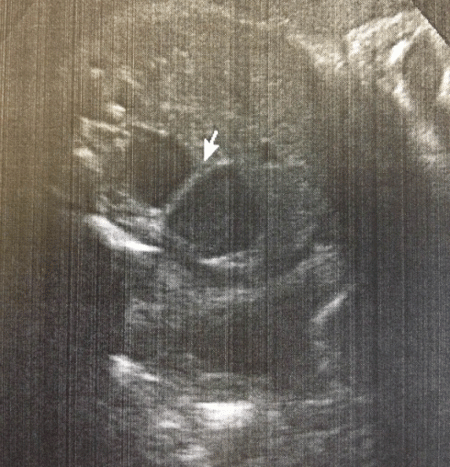

A full-term 2610g male neonate was admitted to the intensive care unit (NICU) with an antenatal history significant for a “double bubble” detected during the second trimester ultra sound examination (Fig. 1). A presumed diagnosis of duodenal stenosis/atresia was made with further karyotyping and anomaly scan showing no abnormalities. The antenatal imaging performed in the third trimester re-confirmed the findings of a double-bubble with no other anomalies being identified. Born at 38 +2/7 weeks, with APGAR scores of 7 and 9, the neonate had mild fullness of the right upper quadrant on clinical exam but no palpable mass. A supine abdominal x-ray revealed a dilated small bowel loop in the right upper quadrant with distal bowel gas, which was interpreted as a possible mega duodenum due to obstruction at that site consistent with the antenatal “double bubble” finding (Fig. 2). Patient then underwent an upper gastrointestinal series (UGI), which initially revealed no evidence of gastric outlet and duodenal obstruction or malrotation. However, subsequent delayed films showed of a space-occupying lesion in the right upper quadrant with a characteristic displacement of small bowel loops. Its subsequent opacification on delayed films was suggestive of a duplication cyst (Fig. 3). No evidence of bowel obstruction was seen. A post-natal ultrasound was not considered necessary in view of the findings on the UGI series.

Figure 1: 22wk prenatal US showing pseudo double bubble. |